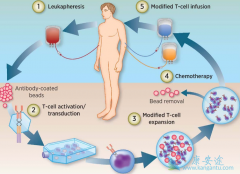

CART疗法 在全球范围内受到包括学者、医生、患者、投资人在内的如此大量的关注和期待,起初是源于一个白血病小女孩Emily和她的神奇抗癌经历。先一起来看看Emily的神奇故事吧! Emily是一位来自美国加州的小女孩,5岁时不幸被诊断为患上了急性淋巴细 ...

CART细胞疗法 在实体瘤中仍需不断探索。CD19 CAR-T细胞是首个获得商业批准的转基因治疗。遗传工程化T细胞作为癌症精准治疗,其中最重要的科学挑战是CAR-T细胞如何治疗实体瘤,目前最突出的例子就是颅内使用IL13RαCAR T细胞治疗多发脑恶性胶质瘤,使肿 ...

CD19 CAR-T治疗是目前最成功、也是最广为人知的CAR-T治疗,从中可得出一些结果:B细胞增生不良说明 CART细胞 也可对正常组织造成损害,虽然CD19 CAR-T治疗的这一副作用并不危胁生命,但其它靶点的其它副作用可能会危胁生命;CD19 CAR-T治疗完全缓解后复 ...

所有癌症治疗均有副反应, CART 细胞也不例外,其毒性主要来自脱靶作用,与抗体单链可变区片段的特异性和T细胞活化有关。当靶细胞被清除或植入的CAR-T细胞消失后,副反应也随之消失,这与传统细胞毒化疗的脱靶毒性作用完全不同。传统化疗毒性可导致组织 ...

靶向CD19 的 CART 是目前最成功,应用最多的细胞疗法。之所以选择CD19作为靶点,是因其频繁表达于B细胞白血病和淋巴瘤,且表达程度和水平远高于其它潜在靶点如CD20、CD22。CD19还可表达于正常B细胞,因此可致B细胞增生不良,可通过输注免疫球蛋白减轻B细 ...

2012年,6岁的急性淋巴细胞白血病小女孩Emily在无药可医的情况下,尝试了Carl June实验室的研究性 CART细胞治疗 ,奇迹至此发生,治疗后她一直健康的生存至今。CD19 CART细胞治疗自此以百米速度进入公众视野和临床实践。其中CAR,即嵌合抗原受体,是该治 ...